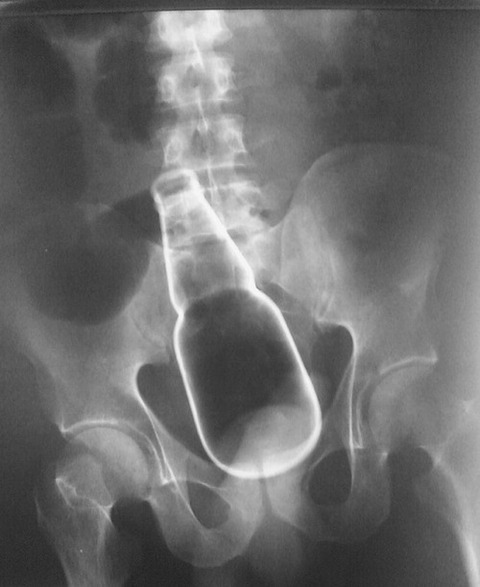

中国のある男性は自身の肛門に“液体のり”を容器ごと挿入。

抜けなくなり、病院に駆けつけるハメになったという。

男性の話からそれが円柱形の容器に入れられた液体のりであることも判明した。

しかし、のりはすでに男性の体内奥深くにまで侵入し、容器も滑りやすい素材で容易には引き抜けない状況。

のりの容器は長さ15センチ、直径5センチほどの大きさだった。